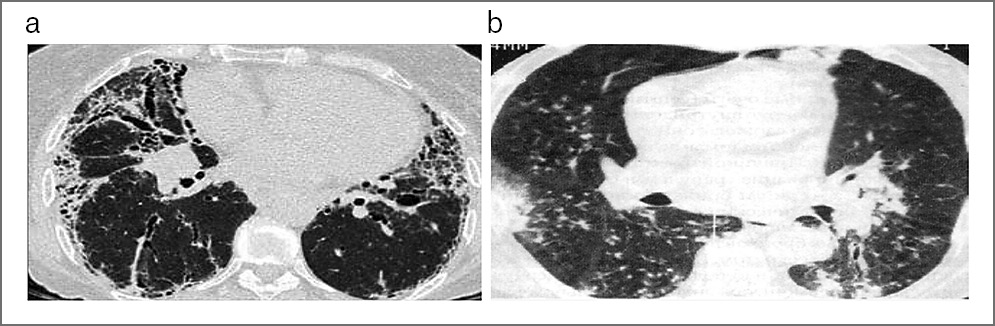

В качестве примеров приводим КТ органов грудной клетки, иллюстрирующую сходство КТ-признаков у больных 1 и 2-й групп, с этиологической верификацией бактериальной пневмонии (вызванной S. aureus) с COVID-19 (рис. 1, а) и без COVID-19 (рис. 1, b); микобактериозом легких (обусловленным M. avium complex) с COVID-19 (рис. 2, а) и без COVID-19 (рис. 2, b); пневмоцистной пневмонией (вызванной P. jiroveci) с COVID-19, ТОД (рис. 3, а) и без COVID-19 (рис. 3, b) и вирусной пневмонией (вследствие инфекции Cytomegalovirus hominis) с COVID-19, ТОД (рис. 4, а) и без COVID-19 (рис. 4, b).

Рис. 1. КТ органов грудной клетки. Аксиальная проекция, режим легочного окна: а – пациент, 36 лет, с 4B-стадией ВИЧ- инфекции в фазе прогрессирования, без АРВТ и верифицированной коинфекции COVID-19, ТОД и бактериальной пневмонией (вызванной S. aureus); b – пациент, 38 лет, с 4B-стадией ВИЧ- инфекции в фазе прогрессирования, без АРВТ и верифицированной коинфекции ТОД и бактериальной пневмонией (вызванной S. aureus).